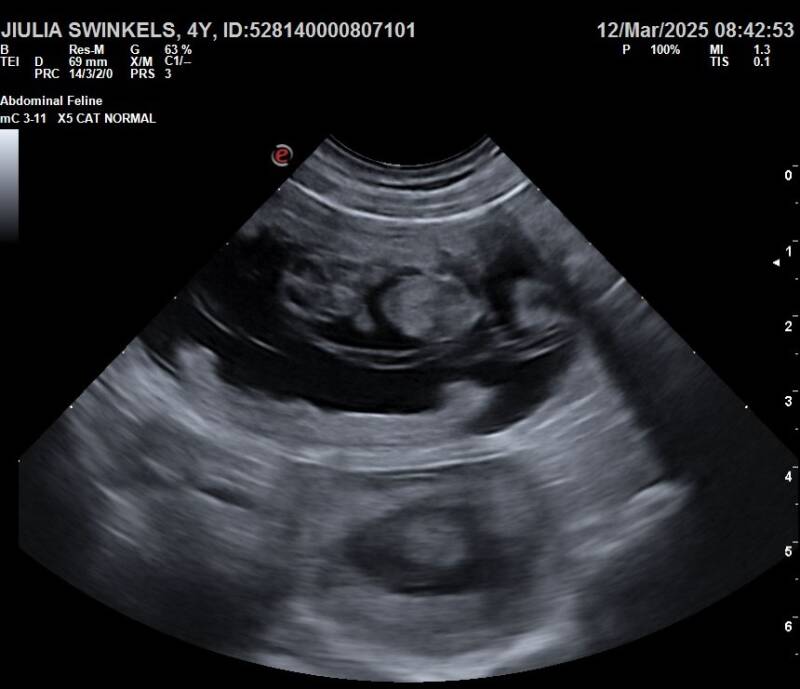

op 12 maart 2025 heeft een echo de dracht van Jiulia bevestigd.

Spannend, en zin in!